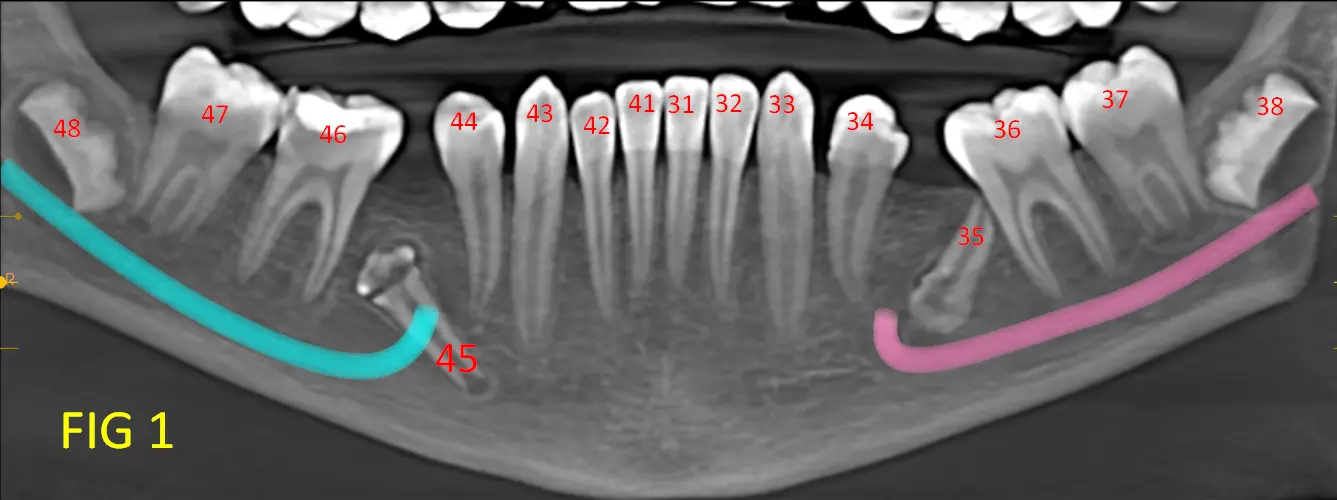

• Pieza 45(Fig. 2) (Fig. 2B): retenida, con posición distoangular.

Ambas piezas presentan adaptaciones morfológicas compatibles con modificaciones ocurridas durante la odontogénesis, probablemente condicionadas por el espacio óseo disponible y las presiones locales.

Estas adaptaciones no representan deformaciones patológicas, sino ajustes estructurales del germen dentario frente a un entorno mecánico restrictivo.